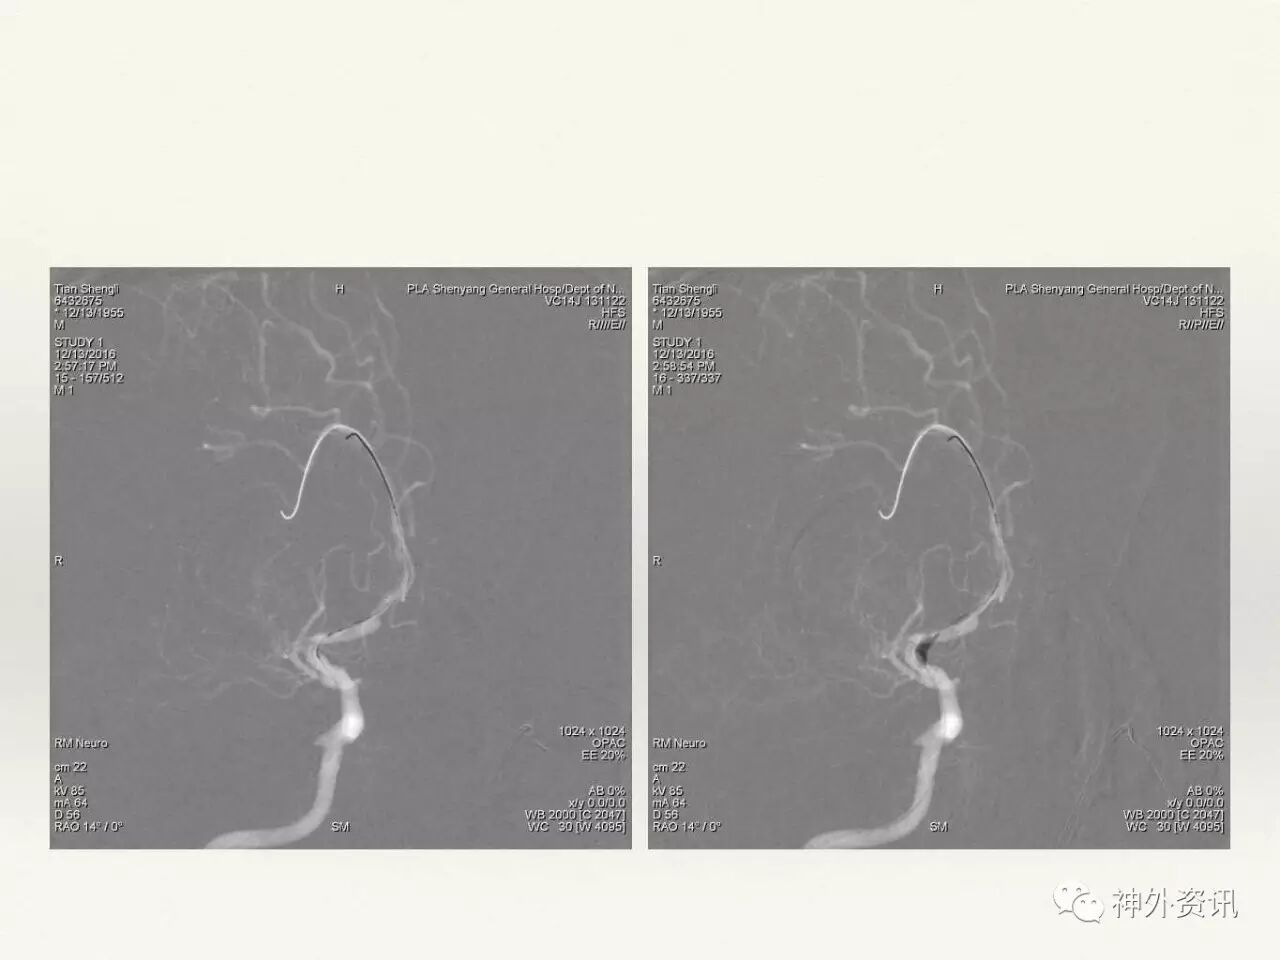

在东北地区率先开展了颈内动脉、大脑中动脉及基底动脉闭塞血管内再通、颅内动脉栓塞急性期取栓、血流导向装置治疗大型宽颈动脉瘤等,对颅内动脉瘤、动静脉畸形、颈动脉及颅内动脉狭窄、颈内动脉海绵窦瘘、硬脑膜动静脉瘘等外科治疗具有较深的造诣。完成脑血管造影8600余例,各类脑血管病介入手术共4500余例,动脉瘤、动静脉畸形、脑肿瘤、脑出血及脑外伤等外科手术1500余例。